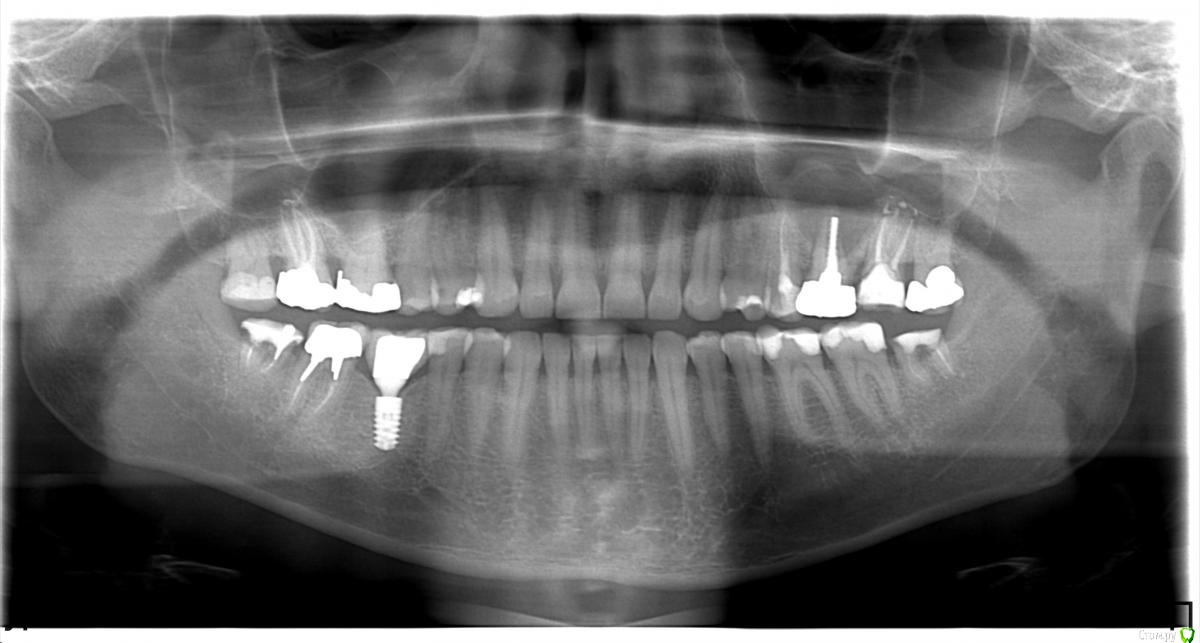

LeoRuss Опубликовано 20 февраля, 2018 Поделиться Опубликовано 20 февраля, 2018 (изменено) Здравствуйте уважаемые метры, в очередной раз обращаюсь к вам за советом.Чуть меньше года назад эндодонтическим методом в полном соответствии с вашими рекомендациями была пролечена киста 26.( http://forum.stom.ru/topic/34508-podsadka-kosti-pri-kiste-nuzhna-li-v-dannom-slucha/ ) При вскрытии зуба выявилась неприятная картина: оба титановых штифта в далеком ‘94м были завернуты мимо корневых каналов прямо в челюсть ;(Док все демонтировал, прочистил под микроскопом и каналы и дыры от штифтов и замуровал МТА : спустя 8 месяцев - 10/2017 : И вроде бы все чудесно, но пару раз за это время десна вокруг зуба воспалялась, и зуб становился более подвижным, но все проходило после 2-3-5 дневного интенсивного полоскания хлоргексидином. Три недели назад была наконец то установлена коронка на соседний 27й, десна с внутренней стороны 26ки тогда была тоже припухшей и протезист посоветовал сходить на контроль к эндодонтисту. Напросился и сходил через неделю, десна за это время еще чуть распухла (только со стороны языка), стало больно при легком нажатии на десну в районе верхушки корня ближнего к 25ке и при покачивании зуба. Док сделал снимок, сказал что все чисто и он понятия не имеет почему все надулось. Вариант удаления забраковал, сказал что по его мнению все хорошо, и можно уже ставить коронку. А вот в импланте смысла никакого, тем более что кости для него пока недостаточно, тк межкорневая область еще не дозаросла. Посоветовал терпеть и.. поставить коронку, тк нагрузка на зуб при жевании должна активировать заживление.Но жевать на этой стороне я стал почти месяц назад, сразу после установки временной коронки на 27, вот с тех пор с 26кой все хуже и хуже. За последние полнедели опухоль сильно увеличилась, и между 25/26, и в сторону нёба, дергает в ритме пульса. Появились отголоски боли в носоглотке и в заглазье.Терпеть уже плохо получается, да и смысла не вижу. Вижу два варианта:1. Удалять 26 чтоб не мучаться, с последующей имплантацией, но как быть с нехваткой кости?2. Вскрыть каналы и прочистить еще раз, но даст ли это хоть что то, да и возможно ли в принципе? В любом случае хотел бы узнать ваше мнение, спасибо ! Изменено 20 февраля, 2018 пользователем LeoRuss Ссылка на комментарий

LeoRuss Опубликовано 20 февраля, 2018 Автор Поделиться Опубликовано 20 февраля, 2018 Как вы и говорили сделали томограмму и все прояснилось: киста зажила наполовину но.. по вертикали, та часть кисты что со стороны щеки затянулась, а вот со стороны языка, только чуть. Видимо повлияла перфорация челюсти штифтом, или МТА туда просто не попало. Увы, теперь уже только удаление. Еще раз огромное спасибо ! Ссылка на комментарий

колесников Опубликовано 21 февраля, 2018 Поделиться Опубликовано 21 февраля, 2018 Удалять с консервацией лунки костным материалом. Киста сделала синуслифтинг в виде купола,надо его сохранить. Если просто удалите зуб-через 3 мес все это исчезнет и для имплантации придётся делать костную пластику. Ссылка на комментарий